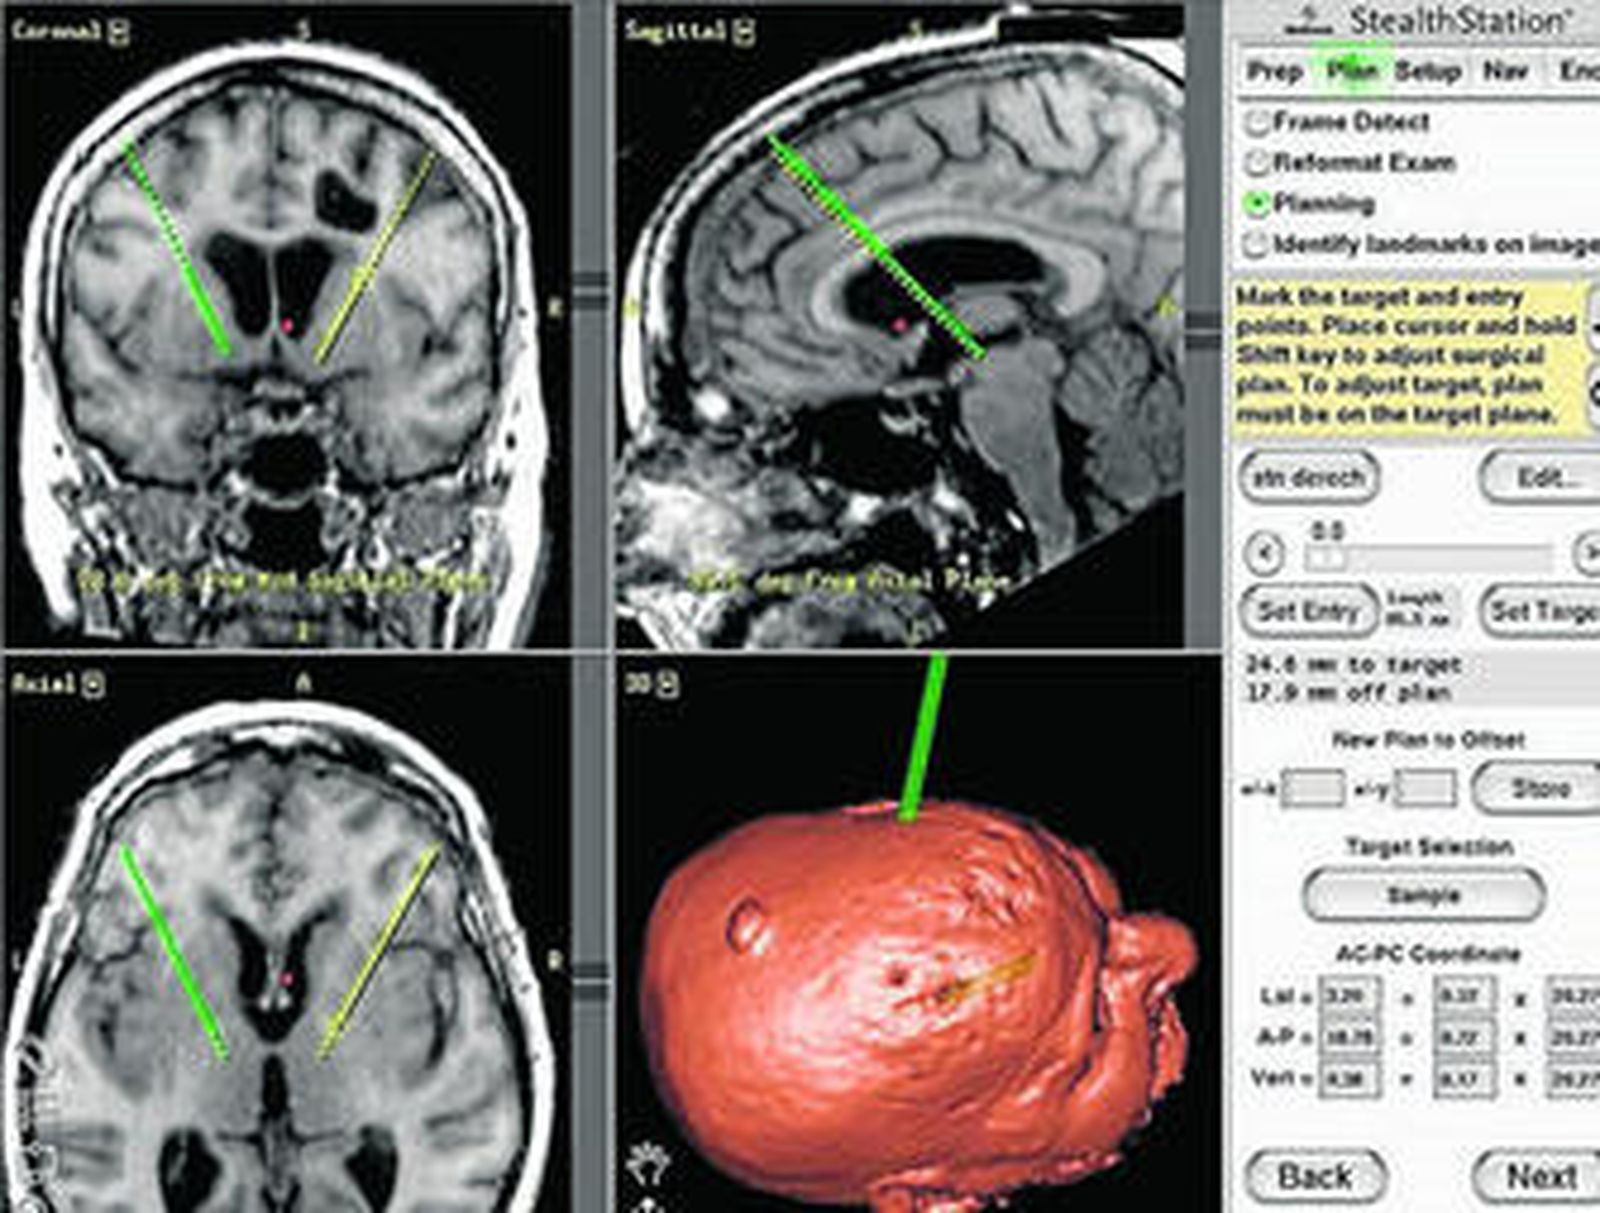

El doctor José Manuel Montero Elena, neurocirujano en Quirón Sagrado Corazón-Iensa, explica que "la cirugía del párkinson comenzó a plantearse en los años 1950 y 1960 para enfermos que no respondían bien a los tratamientos. Esta enfermedad es muy incapacitante". La rigidez y la dificultad para iniciar movimientos, por ejemplo, para comenzar a caminar, son dos de los síntomas que más incapacitan a los afectados. "En los años 90 la cirugía se centraba en realizar lesiones con calor o frío, pero suponía muchos efectos secundarios, que eran irreversibles",añade el doctor Montero. Los enormes avances en este campo ha permitido reducir los riesgos de manera notable gracias, en gran medida, a técnicas de neuronavegación que permiten a los neurocirujanos intevenir con mayor seguridad y exactitud. "Desde la década de los años 90 esta cirugía consiste en la estimulación cerebral profunda", añade. La técnica se centra en colocar unos electrodos en la zona dañada que estimula el cerebro mediante impulsos eléctricos que corregen los problemas motores.